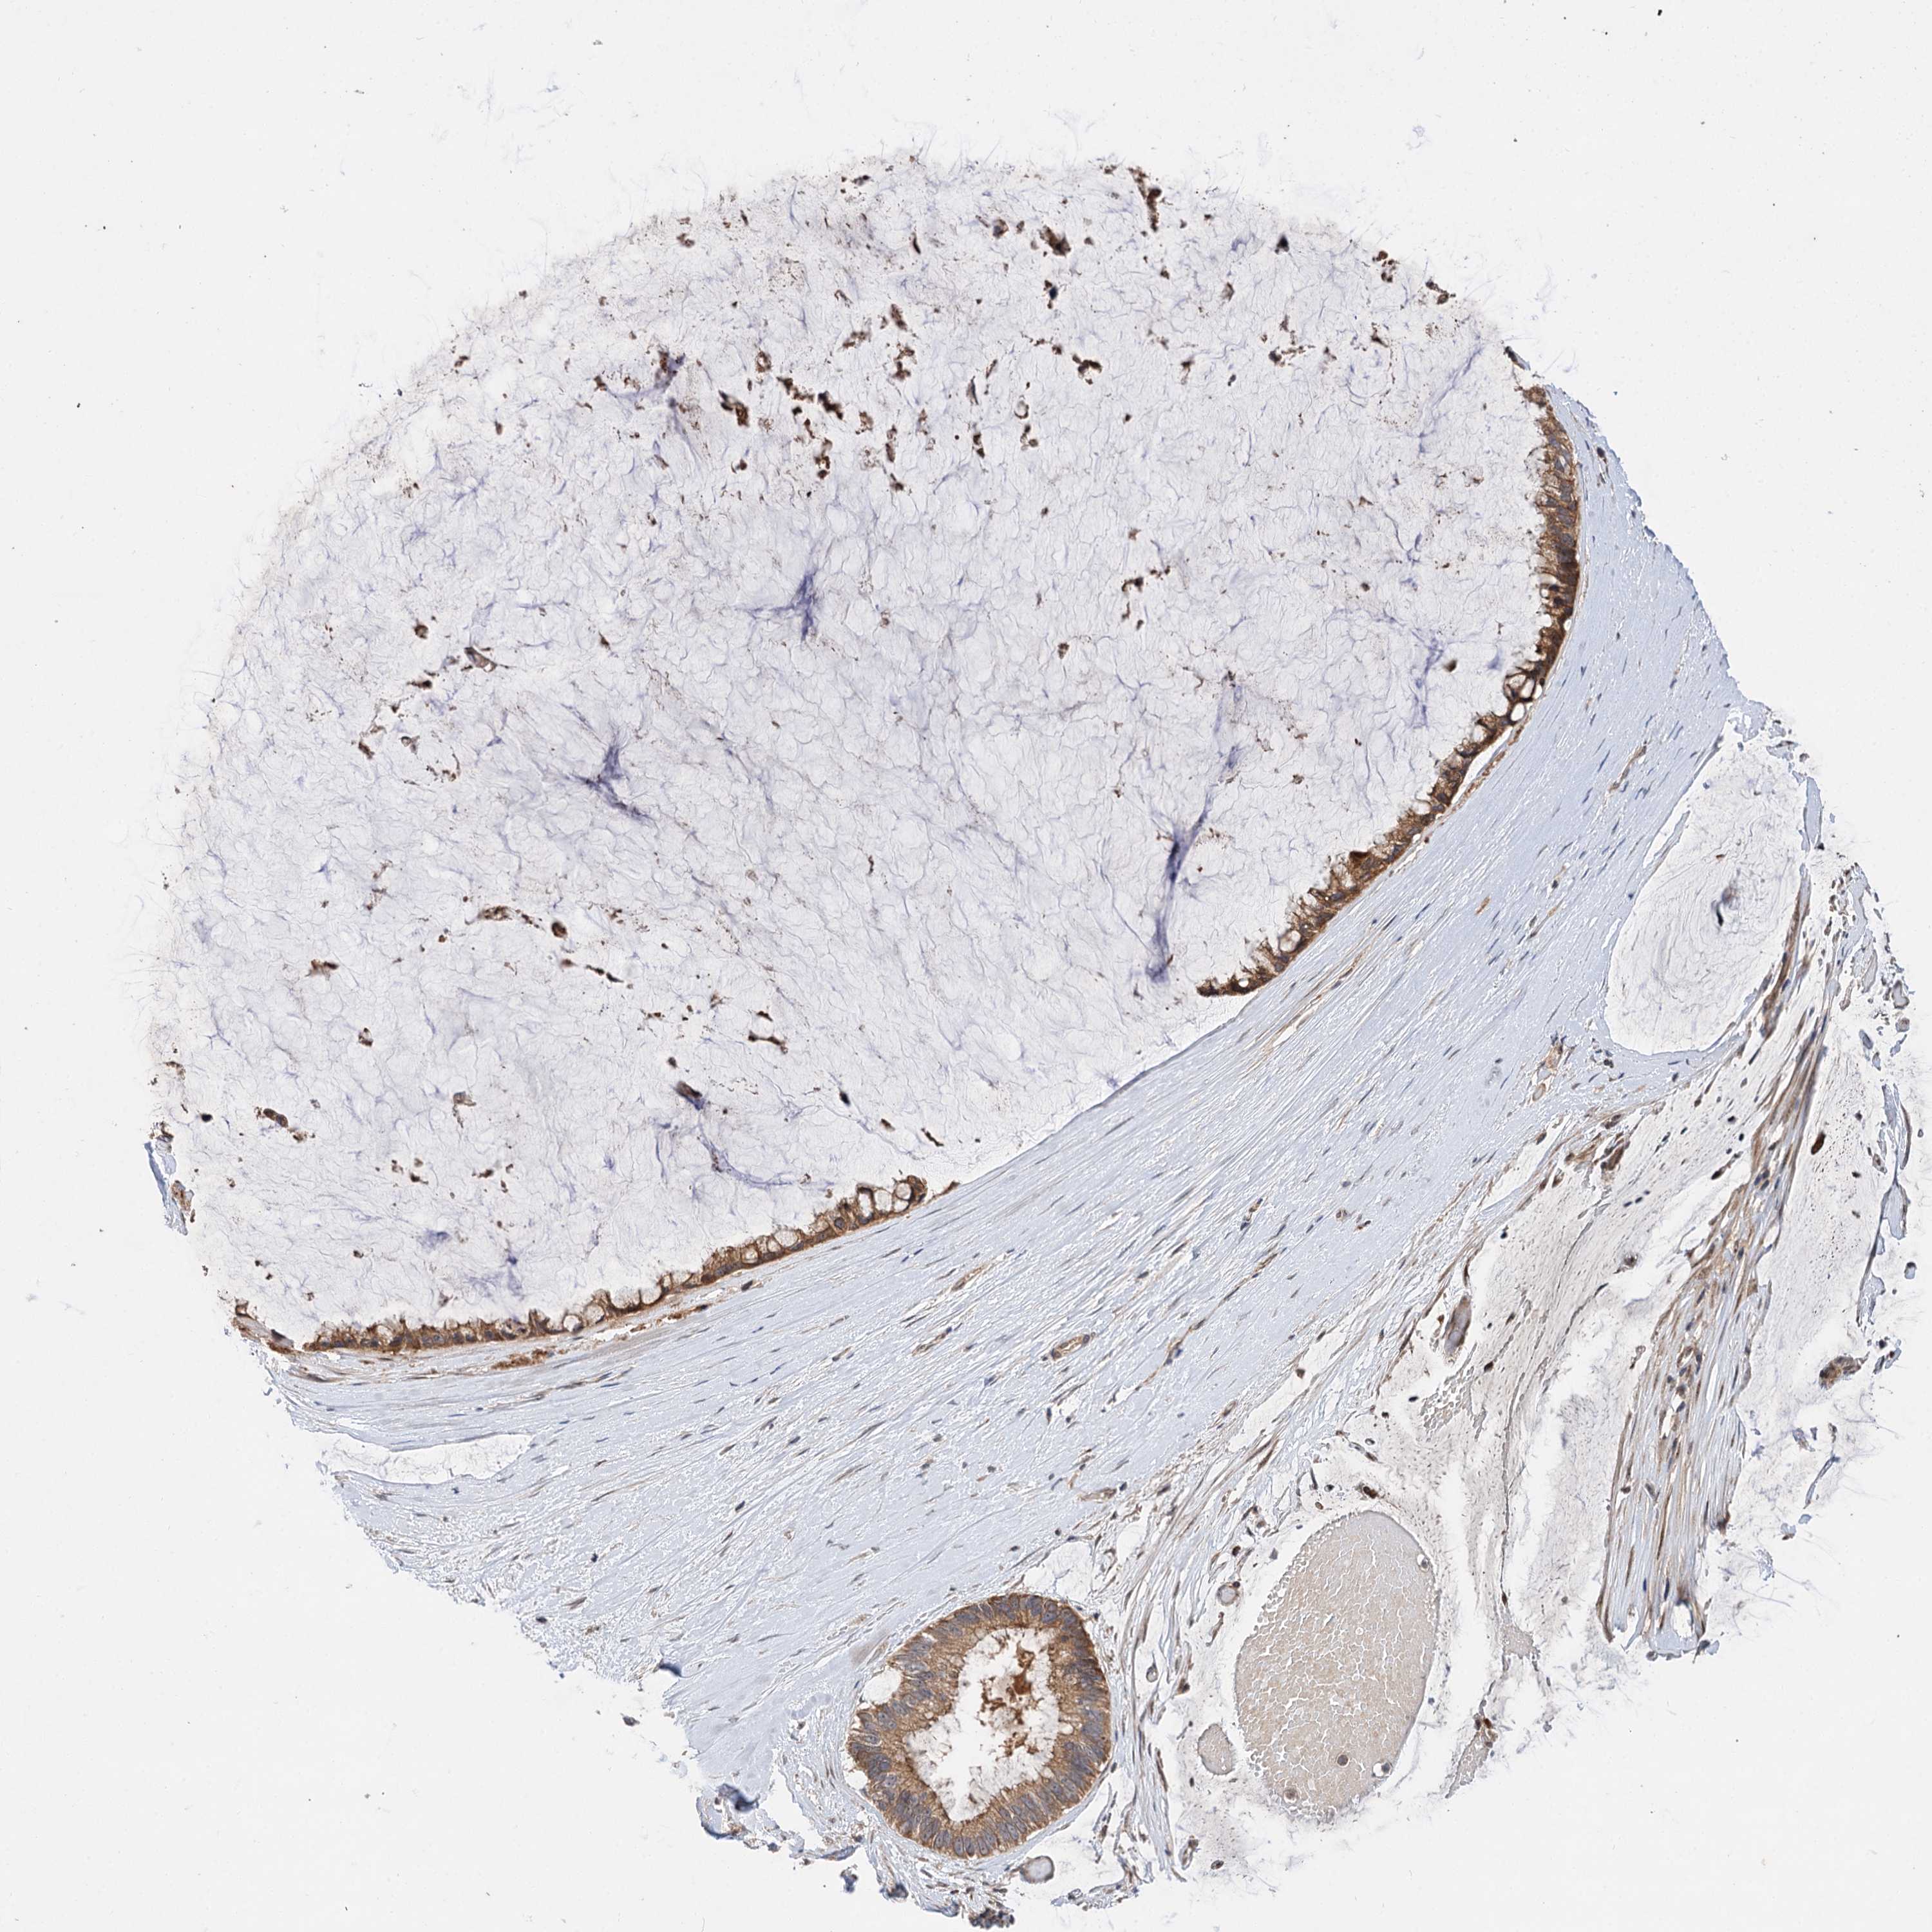

OVARIAN CANCER - Protein expressioni

A mouse-over function shows sample information and annotation data. Click on an image to view it in a full screen mode. Samples can be filtered based on level of antibody staining by selecting one or several of the following categories: high, medium, low and not detected. The assay and annotation is described here.

Note that samples used for immunohistochemistry by the Human Protein Atlas do not correspond to samples in the TCGA dataset.

Antibody stainingi

Antibody staining in the annotated cell types in the current human tissue is reported as not detected, low, medium, or high, based on conventional immunohistochemistry profiling in selected tissues. This score is based on the combination of the staining intensity and fraction of stained cells.

Each image is clickable and will lead to virtual microscopy that enables deeper exploration of all samples and also displays staining intensity scores, fraction scores and subcellular localization as well as patient and tissue information for each sample.

Antibody HPA038850

Antibody HPA038851

Carcinoma, endometroid